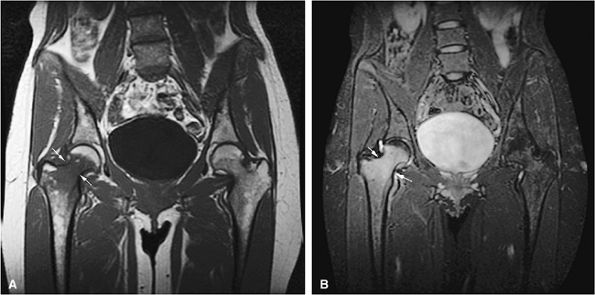

FIGURE 13.18 ● In chronic myelogenous leu-kemia, diffuse marrow involvement infiltrates regions of previous red marrow stores in the femurs (curved arrows) and acetabulum (straight black arrows) and demonstrates low signal intensity on a T1-weighted image (A) and high signal intensity on a corresponding STIR image (B). The sites where yellow marrow is spared (the greater trochanter and femoral epiphysis) demonstrate high signal intensity on the T1-weighted image and low signal intensity (from the nulled fat signal) on the STIR sequence (white arrows).

|